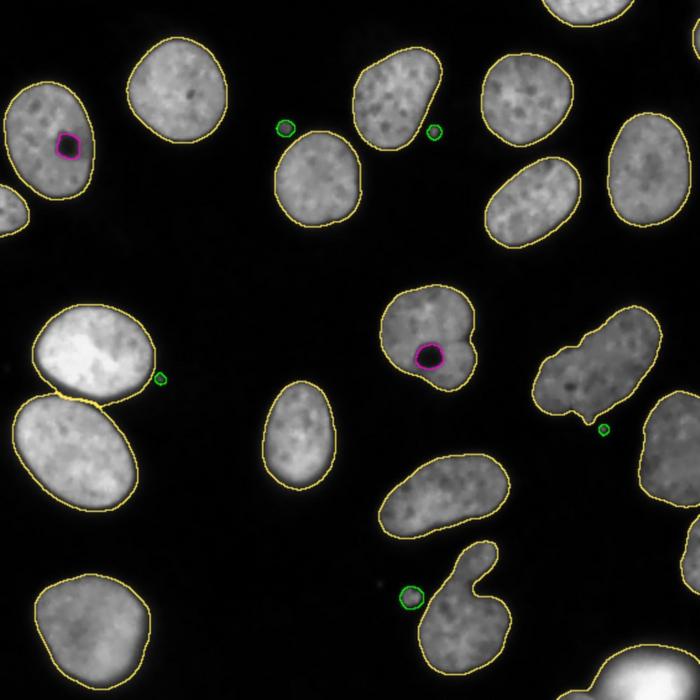

A team of the University of Barcelona (UB) and the Biomedical Research Institute of Barcelona (IRB Barcelona) has designed a new bioinformatics tool to identify the chromosomal alterations that are characteristic of cancer cells. This new detection system, known as QATS (QuAntification of Toroidal nuclei in biological imageS), is a computational biological imaging processing tool that will contribute to improving tumour research and classification through its ability to automatically identify and quantify the phenotypes associated with chromosomal instability in the nuclei of cancer cells.

Cancer cells can survive with high levels of chromosomal instability. The new QATS tool is a predictive system that will help to identify and quantify the toroidal nuclei — new biomarkers of chromosomal instability — in biological images.

“Toroidal nuclei are phenotypically different from normal nuclei, since these present a ring shape and a void with cytosolic material. In the field of research, these have been recently characterized as important biomarkers of chromosomal instability, and they represent an innovative pathway to understand and fight cancer”, notes Professor Caroline Mauvezin, from the UB’s Department of Biomedicine. “Traditionally, the level of chromosomal instability in cancer cells has only been assessed by quantifying micronuclei, which are irregular structures derived from the cell nucleus that may contain chromosomes or chromosomal fragments”, she adds.